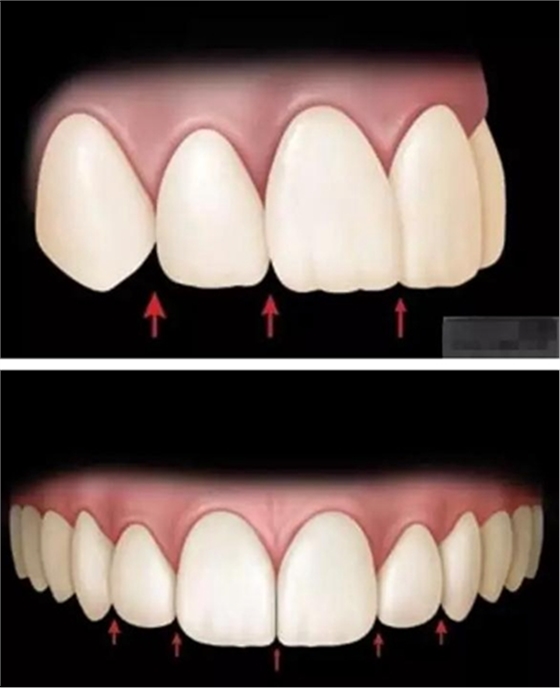

5.外展隙:切端.頸部.唇側(cè)和舌側(cè)

樹脂修復(fù)【診斷蠟型制作】美學(xué)蠟型可以使患者對(duì)可以達(dá)到的修復(fù)效果有直觀的了解,而且,患者也可以依據(jù)自己的美學(xué)素養(yǎng)對(duì)修復(fù)效果提出修改的意見;

制作舌側(cè)背板

使用事先制作完成的硅橡膠模板。它是由技師在做好的美學(xué)蠟型的模型上制作的。這樣的方法為牙醫(yī)提供了許多便利:

a,美學(xué)蠟型可以使患者對(duì)可以達(dá)到的修復(fù)效果有直觀的了解,而且,患者也可以依據(jù)自己的美學(xué)素養(yǎng)對(duì)修復(fù)效果提出修改的意見;

b,應(yīng)用硅膠模板牙醫(yī)可以觀察到牙體預(yù)備量;

c,硅膠模板使牙體修復(fù)簡化,可以首先堆塑牙體的舌側(cè)面,這也是Dr.Vanini分層堆塑技術(shù)的基礎(chǔ),使用硅膠制作的膠刷會(huì)使堆塑更加簡單;